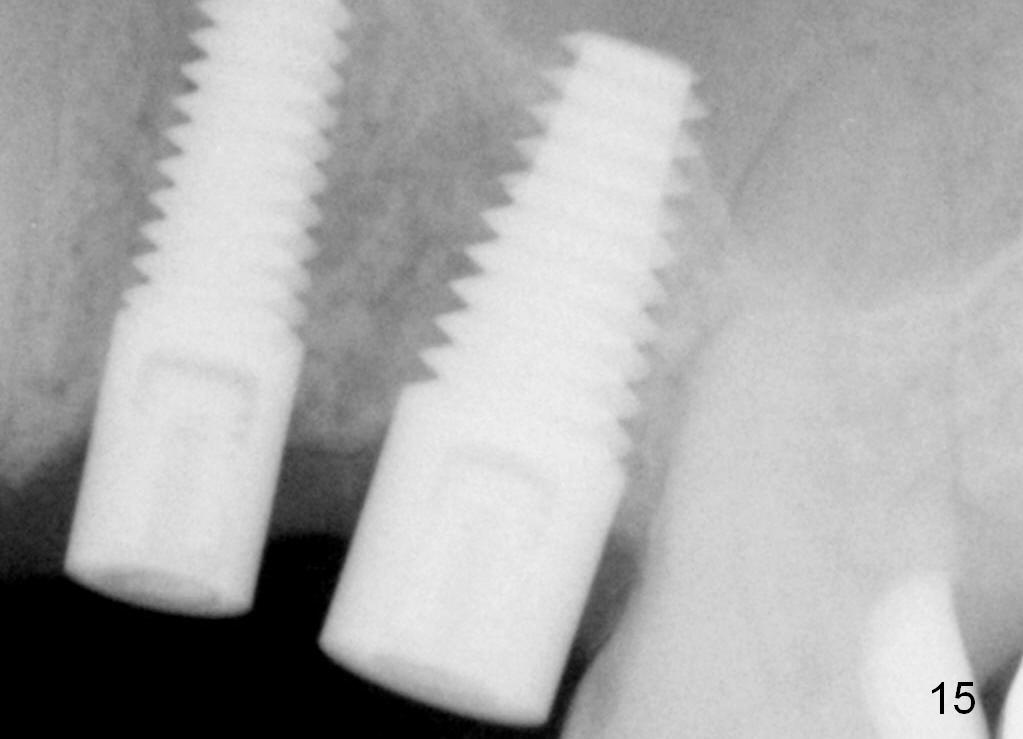

Fig.15 (3 months postop).

Fig.17 (13.5 months postop, 9 months post cementation).  There is minimal bone loss, as compared to Fig.15.